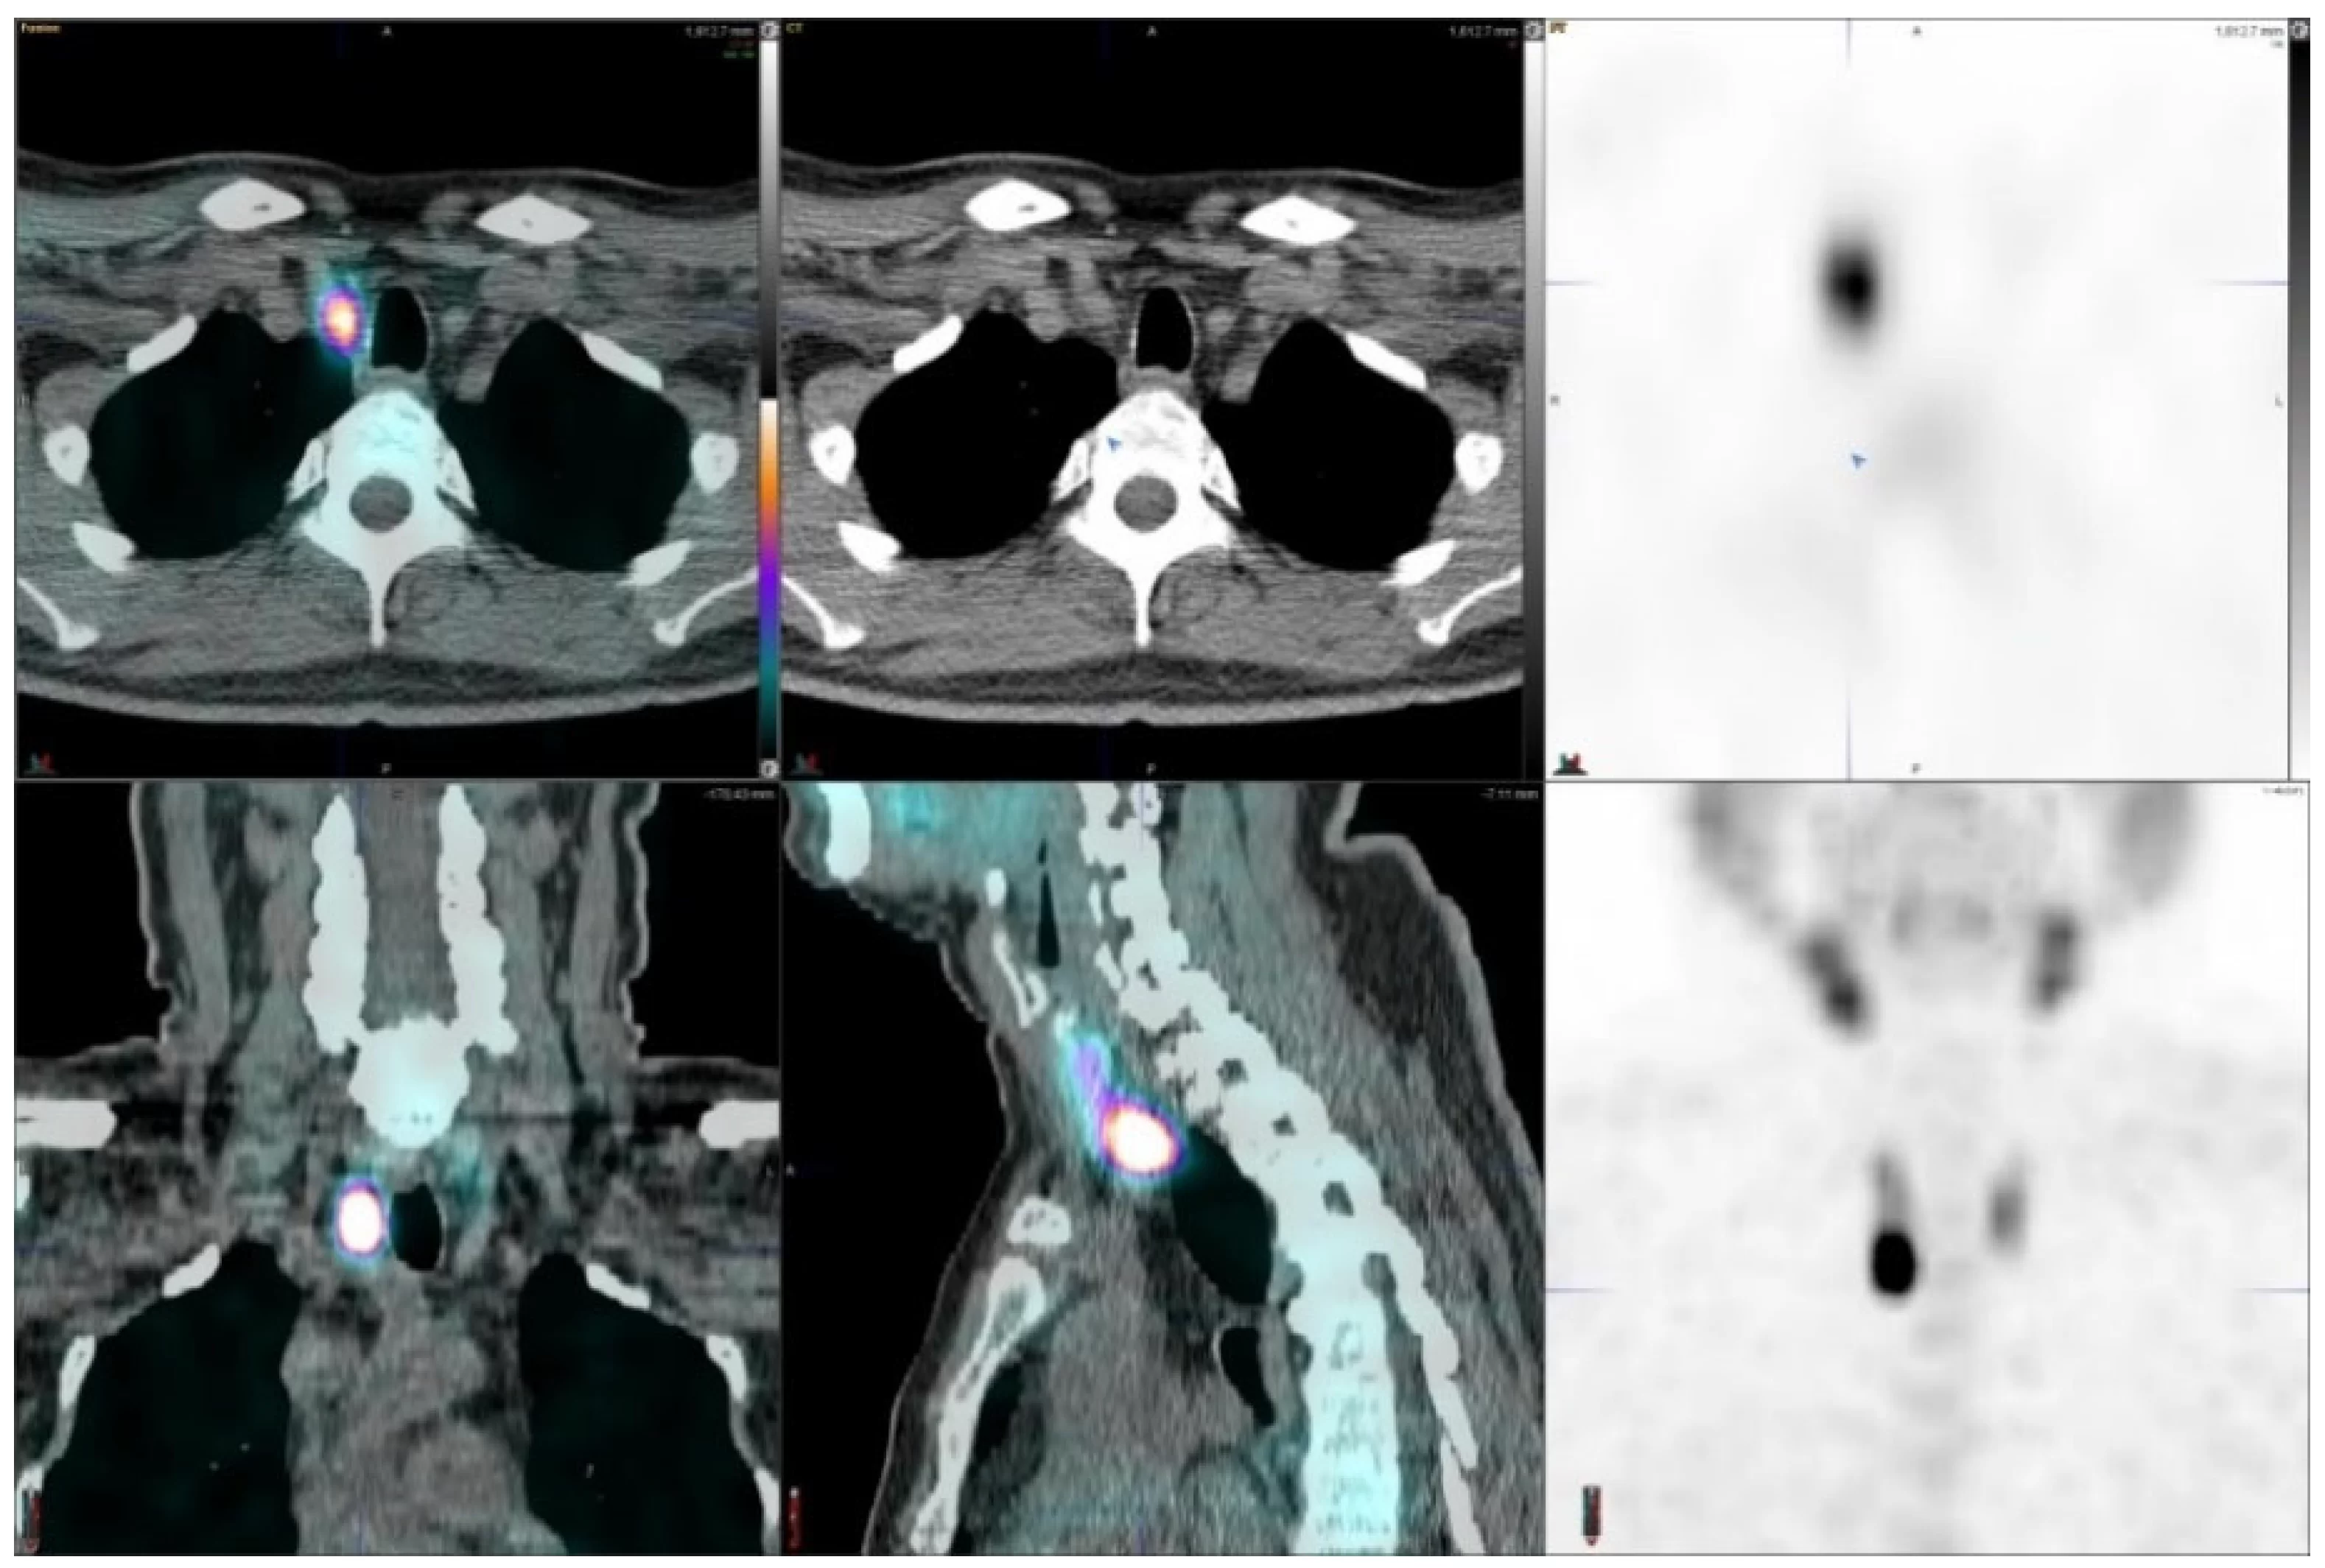

Cintilografia da Tireoide e Pesquisa de Corpo Inteiro com Radioiodo:

- Cintilografia da Tireoide: Avalia a função e a estrutura da glândula tireoide, essencial para o diagnóstico de distúrbios como hipertireoidismo e hipotireoidismo.

- Pesquisa de Corpo Inteiro com Radioiodo (I-131 ou I-123): Utiliza radioiodo para identificar a presença de tecido tireoidiano remanescente ou metastático, especialmente após tratamento para câncer de tireoide.